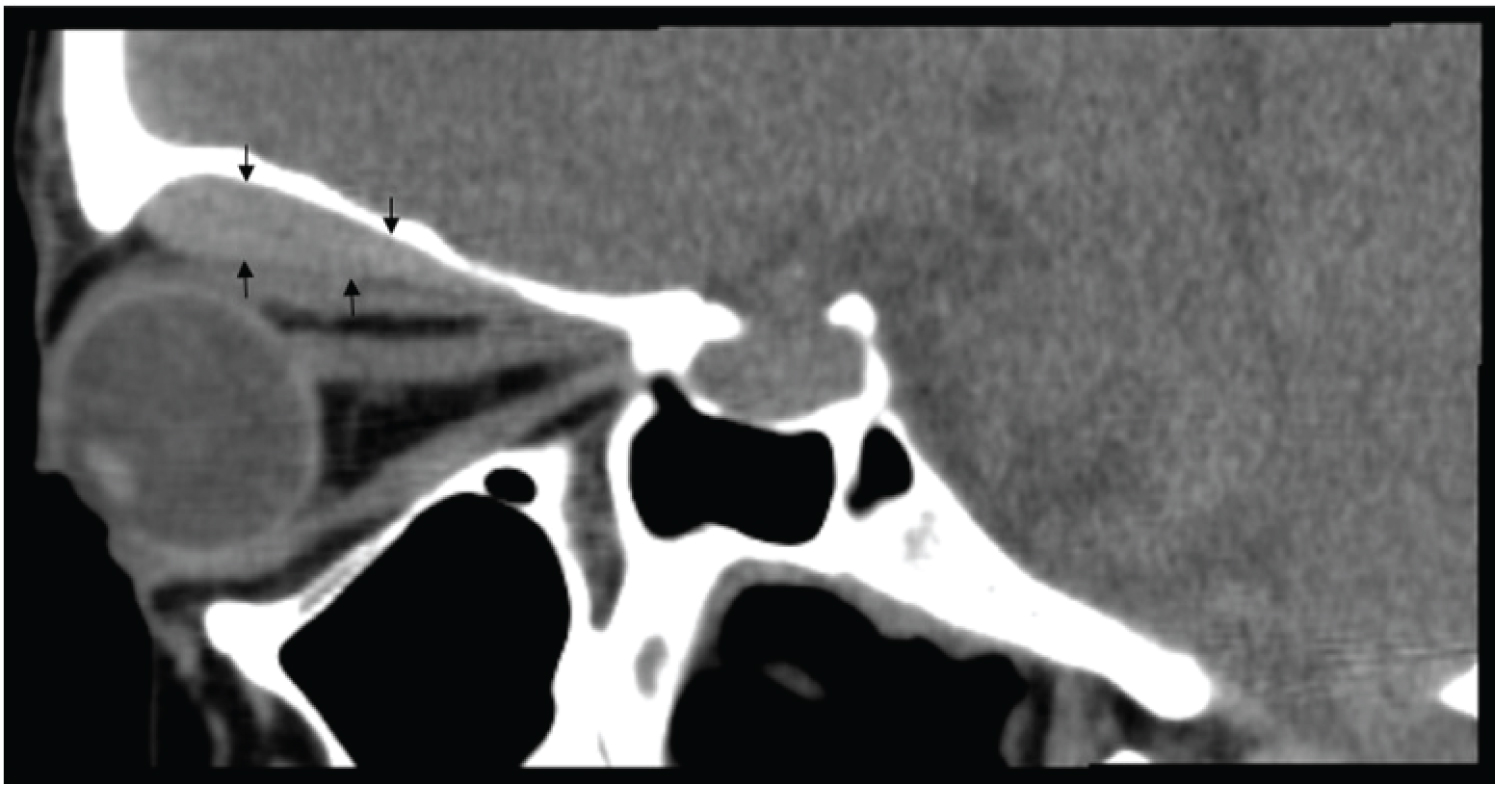

A 34-year-old healthy woman, gesta2 para1, was admitted, at term (39 weeks and 4 days) in our obstetric unit on spontaneous labor. There were no reported complications during the pregnancy and labor developed uneventfully, with normal duration and evolution. Vaginal delivery of a female newborn with normal weight (3160 grams) occurred without need of medical instrumentation. During final expulsive efforts, the mother complained of left ocular pressure and, after delivery, the feeling of double vision. On physical examination, she had an orbital asymmetry with left eye proptosis and inferior deviation. Ophthalmological examination revealed a left vertical diplopia with normal visual acuity (10/10, bilaterally). Pupils were reactive and there was no papilledema. Orbital CT diagnosed a homogeneous, hyperdense lesion with 6.5 × 25 × 34 mm on the left upper orbit, suggestive of hematoma (Figure 1). Orbital/cranial MRI, performed two days later, confirmed an intraorbital, extra-conic acute hematoma with 7 mm (maximum diameter), imposing inferior deviation of left ocular globe (Figure 2). Expectant management was adopted and no other clinical complains were registered.

Figure 1: Hematoma on the left upper orbit (black arrows) on orbital CT. View Figure 1